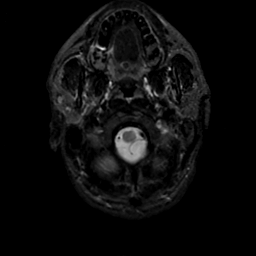

MR Study #18, July 21, 1991 -- Slice #2